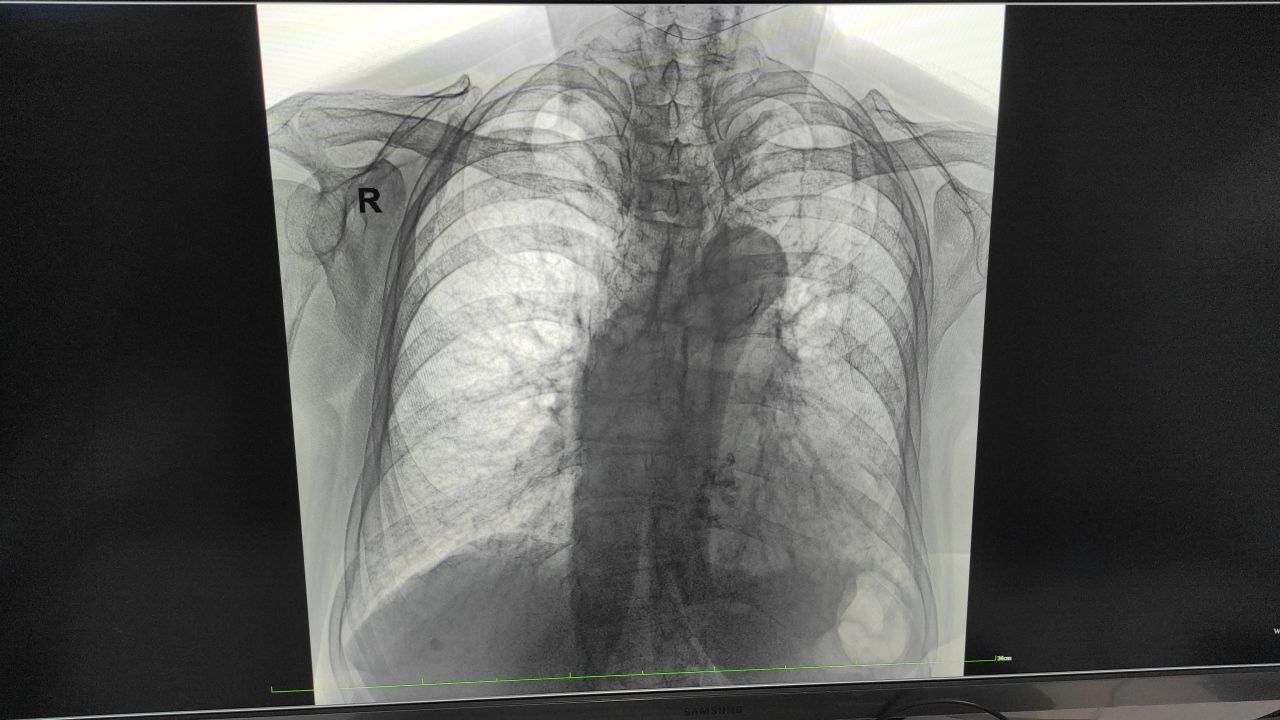

Женщина 83 года

Кашель слабость

Очаговые изменения мерещатся... Есть или нет?

Однозначно пневмония фиброзные тяжи.

Дифференцировать с кардиогенным отёком

Ковид

Полисегментарная интерстициальная двухсторонняя

Частичная релаксация диафрагмы справа